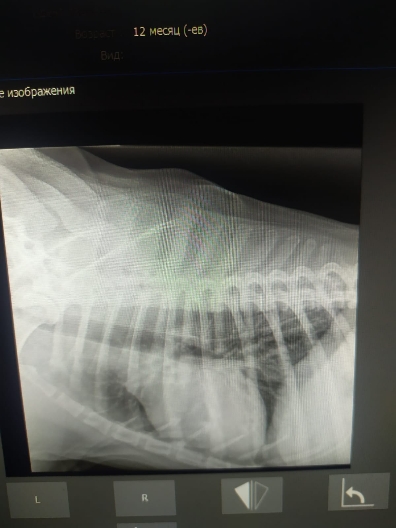

Рентген и анализы.

Юле вчера передали собранное волонтёром на него, 7800р, анализы крови из них оплатила, 510+2090=2600. На остатке у Юли 5200р..

Рентген легких бы еще в другой позиции и на эхо к кардиологу сходить.

Просто на рентгене вопрос к форме сердца.... тогда может рентген на спине попозже